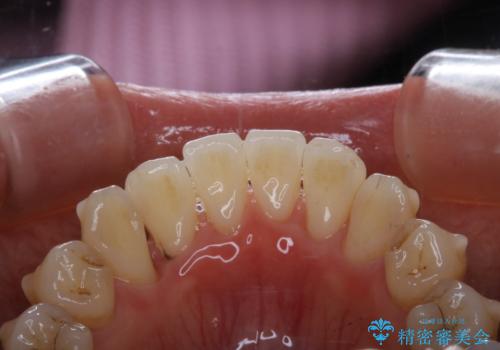

インビザライン中の方 結婚式前にPMTCでステインの除去

- インビザラインでの矯正治療中ですが、結婚式があるため全体の着色・ステインを綺麗にしたいとのことでした。PMTC60分コースを行いました。

PMTC(保険外治療)は、毎日の歯磨きで落としきれない汚れや、コーヒ、紅茶・タバコのヤニなどの着色も除去します。目には見えない歯と歯の間・歯肉の境目・インビザライン中はアタッチメント周囲などに残っているプラーク(歯垢)もしっかり取り除きます。PMTCでは専門的な機械や材料を使用して、徹底的に汚れを除去するため、虫歯・歯周病・口臭予防などにつながります。